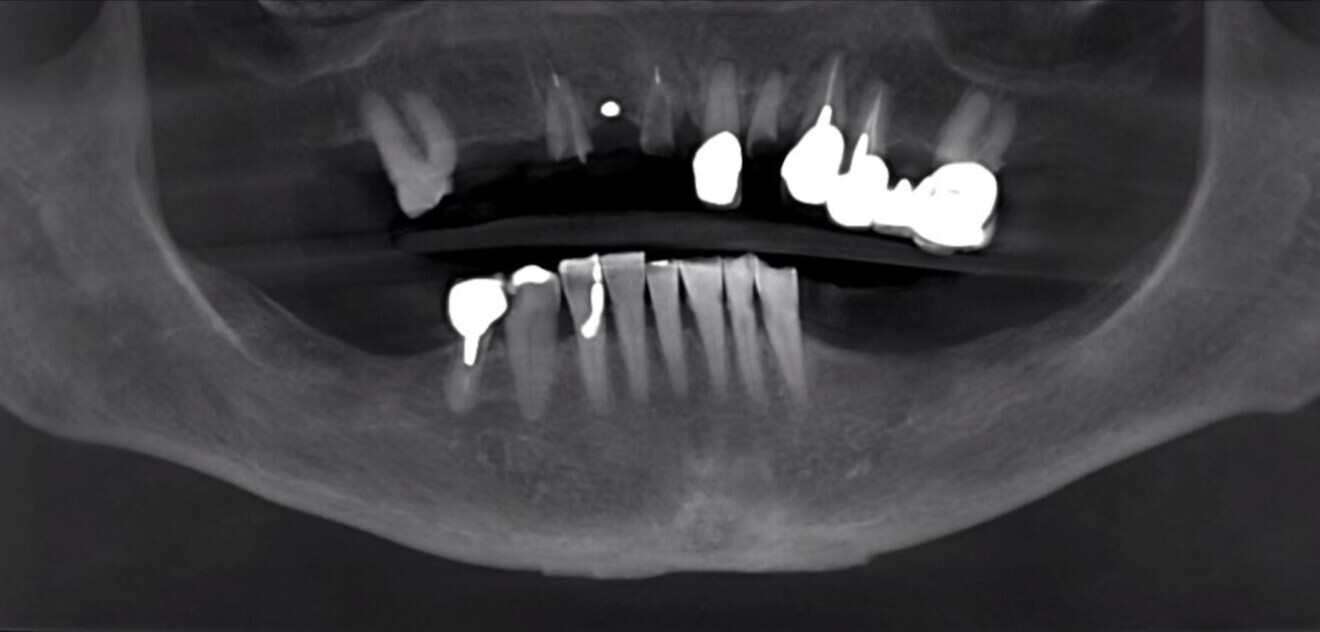

The patient’s medical history revealed hyperthyroidism and hip replacement within the past five years. Clinical examination confirmed the diminished condition of the patient’s dentition, and the need for a thorough 3D assessment of her existing anatomical presentation and that this could only be accomplished with a CBCT scan was explained to the patient. The CBCT scan allowed for the inspection of the anatomy in multiple views and with the digital tools afforded by the software (Carestream 3D Imaging, Carestream Dental; Fig. 1). The panoramic reconstruction served as a scout film to help visualise the condition of the patient’s dentition (Fig. 2). The maxillary arch exhibited several fractured teeth, several that had undergone previous root canal therapy, a single crown and a four-unit posterior bridge on teeth #24, 25, 26 and 27. Using the embedded link, the original CBCT scan data was then exported from the Carestream 3D Imaging software directly to Blue Sky Plan software (Blue Sky Bio). Blue Sky Plan offers additional planning and design tools to aid in accurate diagnosis, treatment planning and surgical guide fabrication.